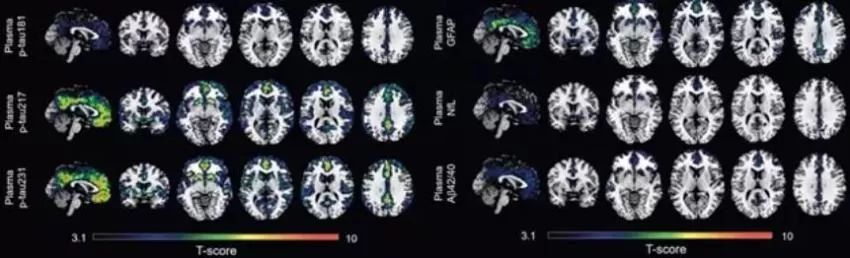

En colaboración con la Universidad de Gotemburgo, los investigadores han desarrollo el nuevo biomarcador en sangre p-tau231 y lo han comparado con otros cinco biomarcadores en sangre --los p-tau181, p-tau217, Ab42/40, GFAP y NfL--, previamente estudiados en la fase sintomática de la enfermedad de Alzheimer.

Este es el primer estudio que investiga todos estos biomarcadores en la fase preclínica de la enfermedad de Alzheimer, y los resultados muestran que p-tau231 y p-tau217 son los mejores biomarcadores en sangre para detectar los primeros signos de acumulación de amiloide en el cerebro.

El estudio indica que los biomarcadores en sangre p-tau231 y p-tau217 mostraron la asociación más fuerte con la retención de amiloide en regiones de acumulación temprana en el cerebro y se asociaron con aumentos longitudinales en la captación de esta proteína en individuos sin patología amiloide manifiesta al comenzar el estudio.